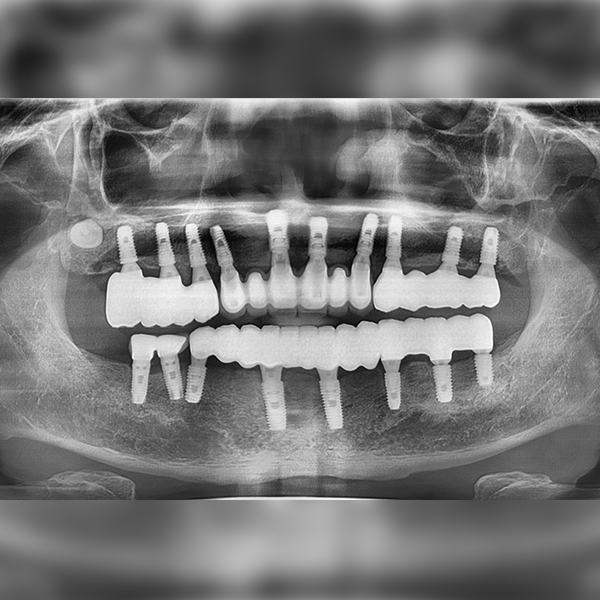

上顎/前牙部位 / 4顆以上 / 補骨|舒眠|高血壓

案例155 60多歲 鄭*澤 2022-04-23 / 2019-11-28